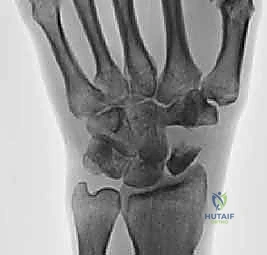

Radiographs, while not always definitive in early stages, provide crucial information.

* PA View: We look for a scapholunate gap >3mm or wider than the contralateral side, and the cortical "ring" sign.

* AP View (Clenched-fist): This view accentuates the scapholunate gap by applying axial load.

FIG 2 • A. Clenched-fist PA view with the wrist in supination, demonstrating a significant increase in the scapholunate interval space.